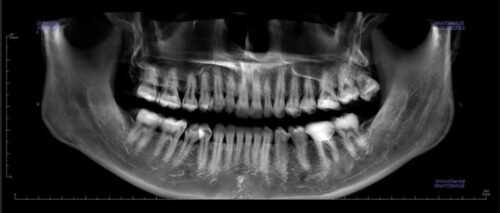

Hình 3: Chụp XQ nha khoa được cho là an toàn khi sử dụng áo chì

Kiểm tra sức khỏe răng miệng định kỳ giúp phụ nữ mang thai theo dõi tình trạng răng miệng và nhận lời khuyên từ bác sĩ. Chụp X-quang nha khoa được coi là an toàn khi sử dụng áo chì bảo vệ, giảm thiểu tác động của tia X lên thai nhi.